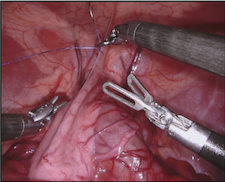

As robotic minimally invasive surgery has developed, with platforms such as da Vinci becoming the de-facto standard-of-care for certain urological, gynecological and general surgical procedures, there has been an increase in focus in how assistive systems based on computer vision and machine learning can improve surgeon performance and patient outcomes. Many potential applications are dependent on scene understanding and for this, accurate segmentation of instruments is an important component. For instance, instrument tracking algorithms which underlie automation and guidance assistance often build upon segmentation [4] or alternatively masking augmented reality overlays of 3D imaging modalities requires pixel labelling of the instruments to prevent their occlusion (see Fig. 1).

In 2017 we organized a follow-up challenge222https://endovissub2017-roboticinstrumentsegmentation.grand-challenge.org where a team at Intuitive Surgical manually segmented images from porcine robot assisted nephrectomy procedures. We aimed to improve on the previous challenge by first increasing the label quality by using hand-created labels rather than automatic labelling, secondly by adding greater variance in the background by using 10 separate procedures and finally by providing more type and part labels for the instruments.

Our dataset was made up of 10 sequences of abdominal porcine procedures recorded using da Vinci Xi systems. From each procedure we selected active sequences where significant instrument motion and visibility was observed and sampled 300 frames at a rate of 1 Hz. In cases where instrument motion ceased for several frames we manually removed these frames and extended the sequence so that exactly 300 frames remained. We provided left and right eye images from the stereo camera on the Xi system and also provided camera calibration information in case participants wished to use stereo reconstruction as a feature.

We provided the first 225 frames of 8 sequences as training data and kept the last 75 frames of those 8 sequences as test data. 2 of the full 300 frame sequences were kept as test sequences. Test labels were kept hidden from the participants. Our datasets contain 7 different robotic surgical instruments. The Large Needle Driver, Prograsp Forceps, Monopolar Curved Scissors, Cadiere Forceps, Bipolar Forceps, Vessel Sealer and additionally a drop-in ultrasound probe, which is typically held in the jaws of the Prograsp Forceps instrument. Samples from the training datasets are depicted in Fig. 2 and examples of the different instrument types are shown in Figure 3 and 4.